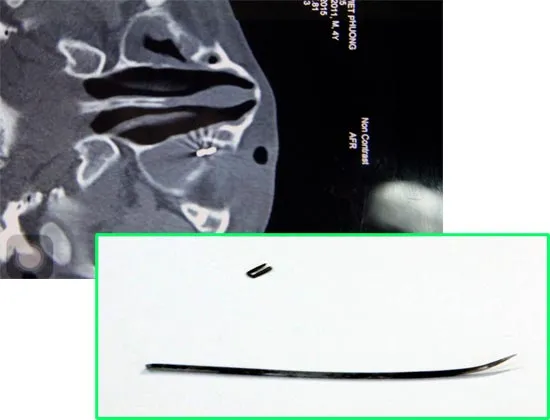

Ảnh chụp dị vật và dị vật được lấy ra.

Người nhà cho biết trong khi đang nằm chơi trên võng thì cháu bé 4 tuổi, ngụ tỉnh Sóc Trăng bị té sấp. Cây kim may bao (còn gọi là cây lẹm) đang cắm trên tấm dừa nước đã đâm thẳng vào bên dưới con mắt trái. Phần đuôi cây kim bị gãy có hình chữ U với chiều dài khoảng 10,5mm ghim sâu vào hốc mắt.

Nguyên nhân là dị vật nhiều lần di chuyển nên dù đã siêu âm đánh dấu vị trí nhưng khi phẫu thuật thì dị vật lại di chuyển chỗ khác. Trong lần phẫu thuật thứ 3, các bác sĩ buộc phải chụp CT thì mới xác định chính xác vị trí của đuôi cây kim lúc này đã được cố định sau khi đâm vào bờ dưới xương hốc mắt của cháu bé.

Sau 8 ngày nằm trong hốc mắt, dị vật đã được lấy ra trong tình trạng đã rỉ sét. Tuy nhiên, do sử dụng kháng sinh nên cháu bé không bị nhiễm trùng.